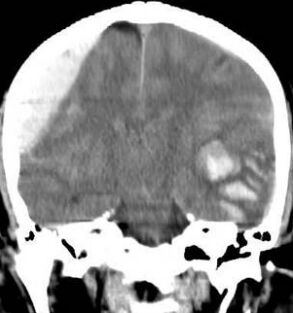

10.承上題,brain CT做完後如附圖所示,下列敘述何者錯誤? (A)左腦為epidural hematoma,右腦為contused intracranial hematoma (B)右腦的出血來源多半為顱骨骨折造成中腦膜動脈(middle meningeal artery)破裂而產生 (C)左腦的出血來源多半為大腦本身的血管破裂而產生 (D)若病人的瞳孔出現放大的情形,則建議進行開顱減壓手術